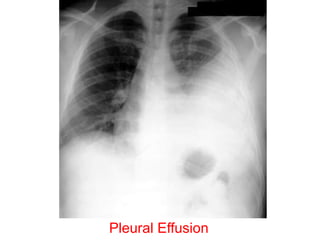

• Chest X-ray PA view showing dense

homogenous opacity at the Rt lung base with

curved upper border, blunting the

costophrenic angle and ascending towards the

axilla. Suggestive of Rt Pleural Effusion

• Around 200 mL of fluid is required in order for

it to be detectable on a PA chest X-ray.

Pleural Effusion